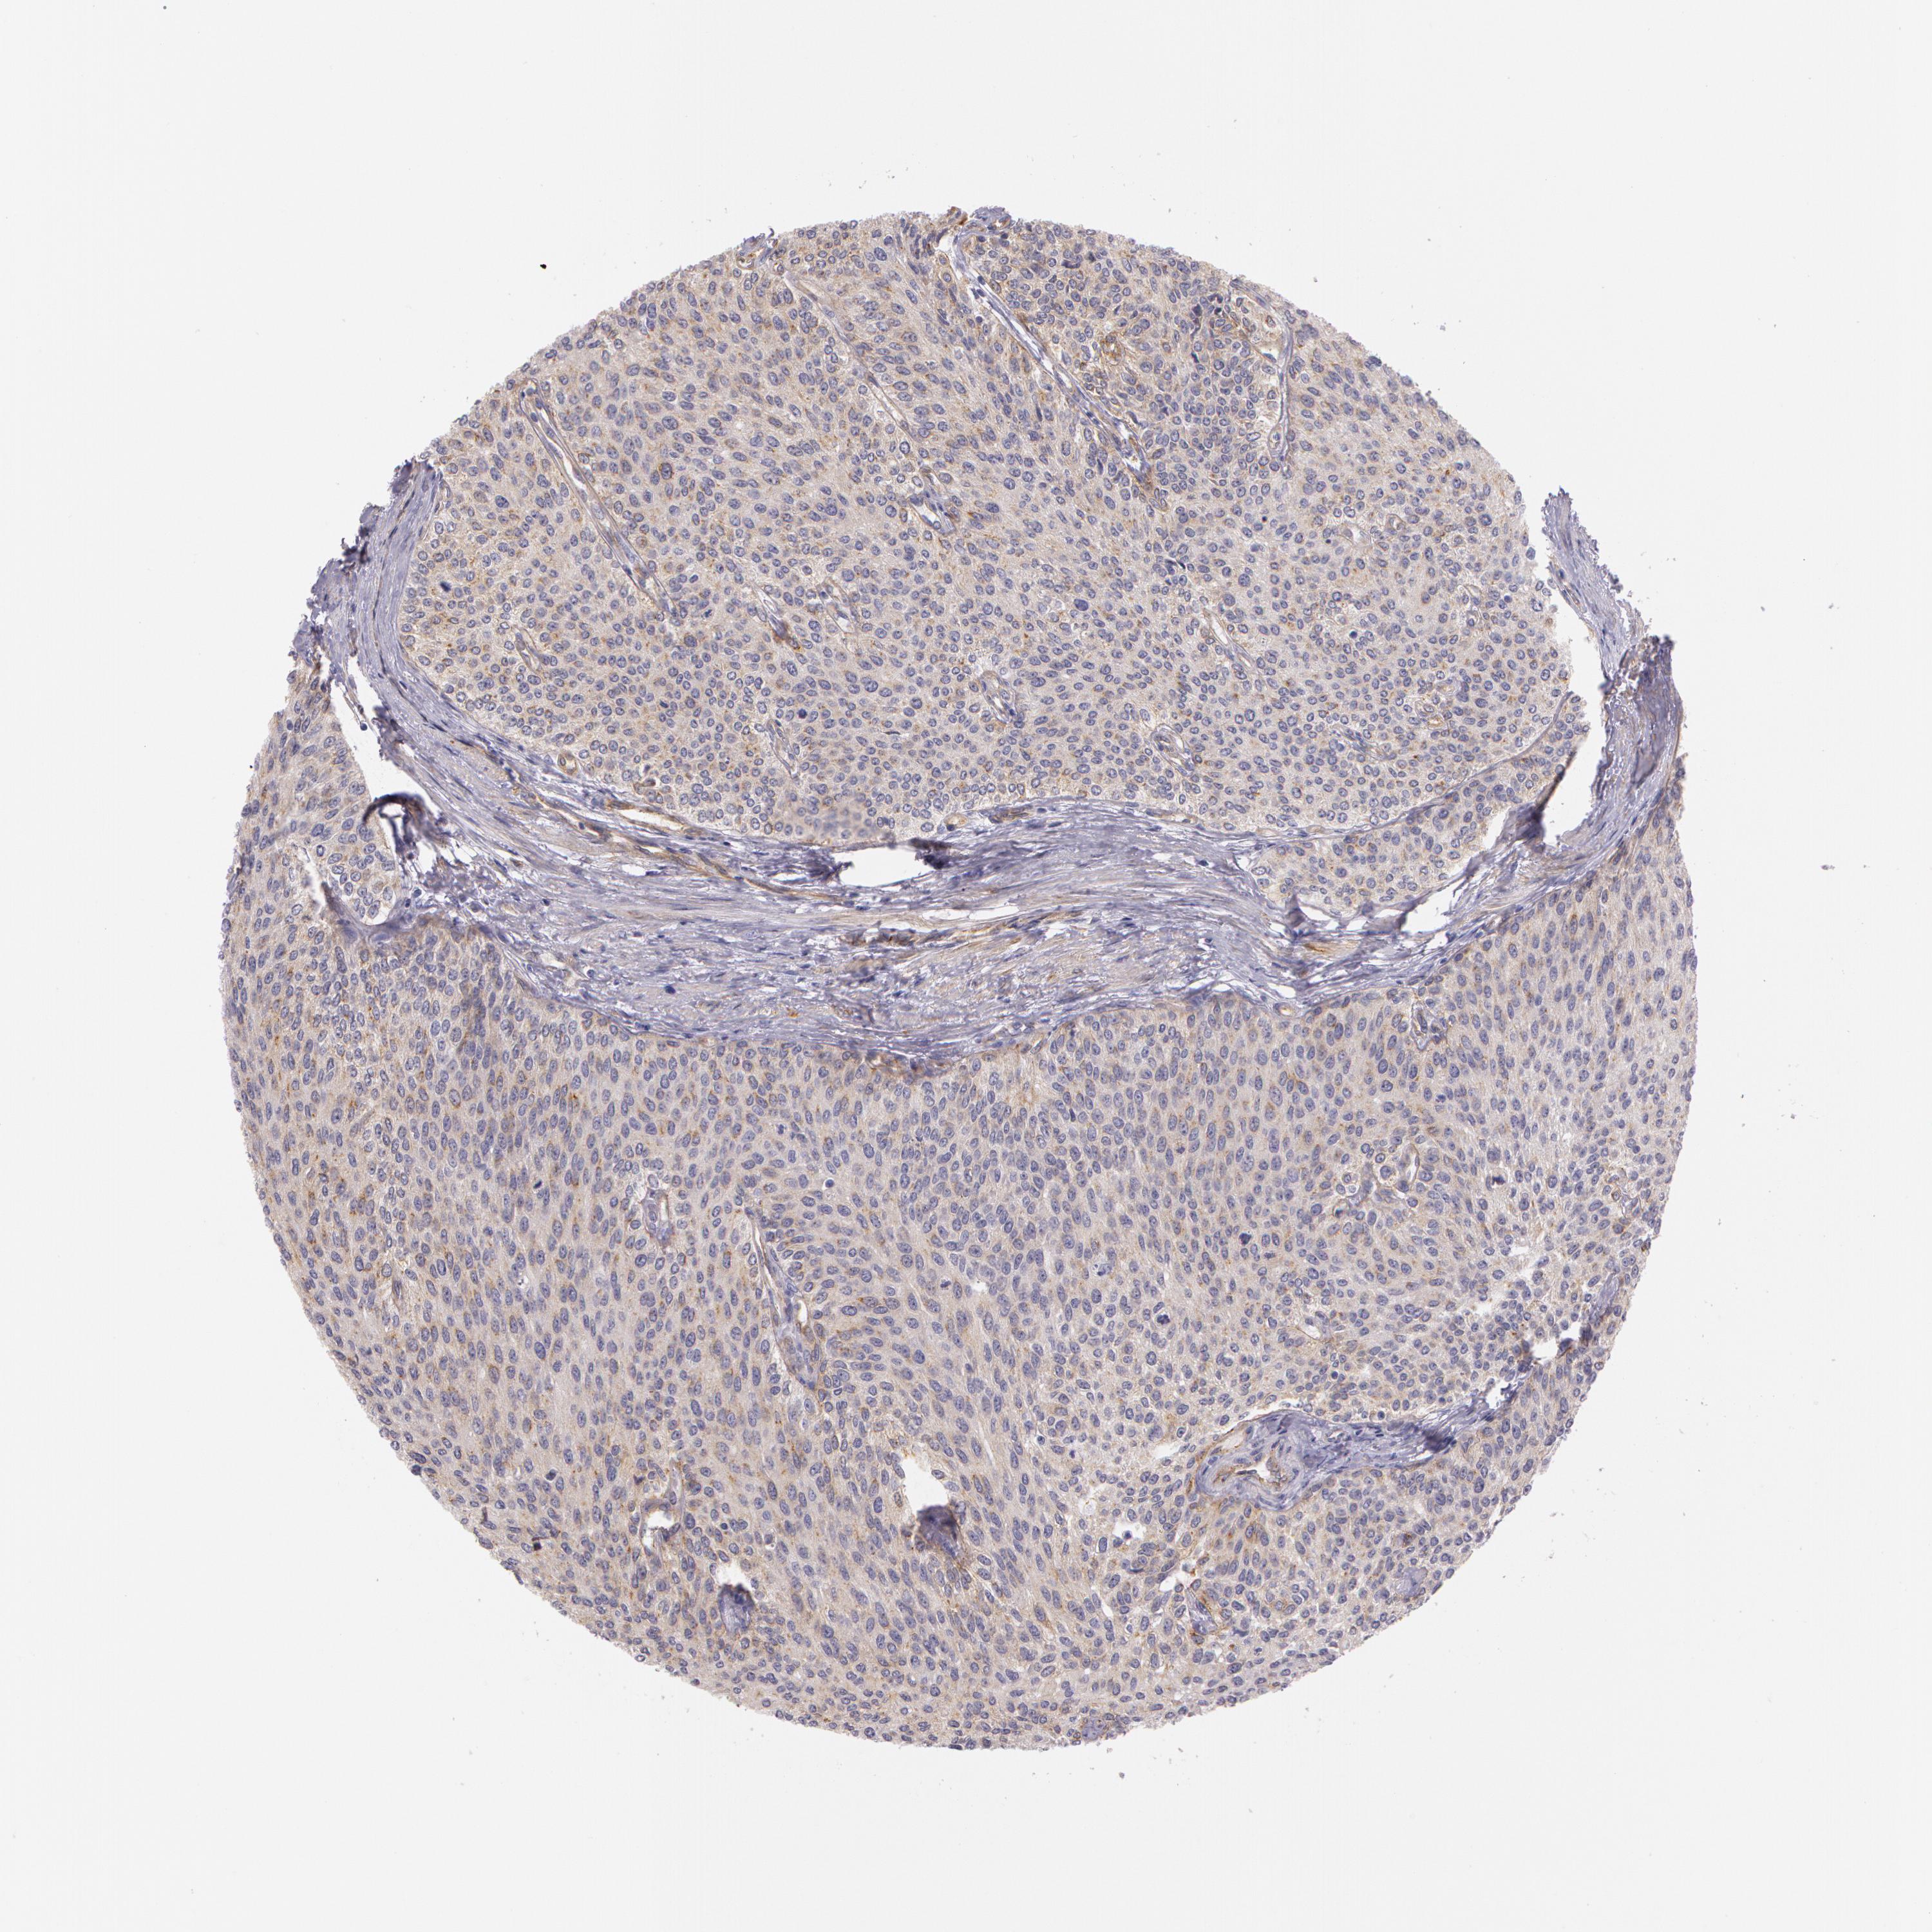

UROTHELIAL CANCER - Protein expressioni

A mouse-over function shows sample information and annotation data. Click on an image to view it in a full screen mode. Samples can be filtered based on level of antibody staining by selecting one or several of the following categories: high, medium, low and not detected. The assay and annotation is described here.

Antibody stainingi

Antibody staining in the annotated cell types in the current human tissue is reported as not detected, low, medium, or high, based on conventional immunohistochemistry profiling in selected tissues. This score is based on the combination of the staining intensity and fraction of stained cells.

Each image is clickable and will lead to virtual microscopy that enables deeper exploration of all samples and also displays staining intensity scores, fraction scores and subcellular localization as well as patient and tissue information for each sample.

Antibody HPA001462

Antibody CAB000157

Urothelial carcinoma, High grade

Urothelial carcinoma, Low grade

Adenocarcinoma, NOS